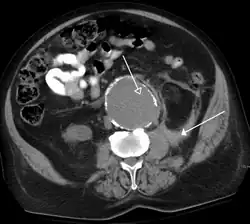

Kidney masses

Detection and characterization of renal parenchymal masses is a frequent indication for CT. An initial noncontrast CT is important for detecting calcium or fat in a lesion, and to provide baseline attenuation of any renal masses. Following noncontrast scanning, intravenous contrast is injected and a corticomedullary phase is obtained at approximately 70 seconds (figure 7a, 7b). The corticomedullary phase is characterized by enhancement of the renal cortex as well as the renal vasculature. This phase is valuable in the evaluation of benign renal variants, lymphadenopathy and vasculature, however certain medullary renal masses may not be visible during this phase due to minimal enhancement of the medulla and collecting system. The parenchymal phase is obtained approximately 100–200 seconds after the injection of contrast material (figure 7c). Parenchymal phase imaging demonstrates continued enhancement of the cortex, enhancement of the medulla, and various levels of contrast material in the collecting system. The parenchymal phase is highly important for the detection and characterization of renal masses, parenchymal abnormalities, and the renal collecting system. This method of imaging does not evaluate for abnormalities of the collecting system.

Common renal masses can occasionally be differentiated from each other using this imaging technique. Renal cell carcinomas and oncocytomas typically demonstrate intense heterogeneous enhancement on the parenchymal phase images and cannot be reliably differentiated from each other but can be distinguished from other renal masses. Angiomyolipomas (AML's) also demonstrate intense contrast enhancement but characteristically contain macroscopic fat which can be detected on the noncontrast images, and can help to differentiate AML's from renal cell carcinomas and oncocytomas. Renal lymphoma on the other hand, will often have decreased enhancement when compared to the renal parenchyma on the parenchymal phase images.

FIGURE 7. Selected images from a renal mass specific protocol CT. Corticomedullary phase (axial 7a) demonstrates peripheral enhancement of the renal cortex with minimal opacification of the renal medulla. There is a large renal cell carcinoma in the left kidney (right in image) which can be differentiated from the normal renal parenchyma by the heterogeneous and differential enhancement. The renal artery and vein are opacified in this phase as well. The collecting system is not opacified (coronal reformat 7b). In the parenchymal phase, the renal cortex and the medulla are enhancing. The renal cell carcinoma in the left kidney is not as well defined when compared to the corticomedullary phase images, but is actually slightly more conspicuous. There is some contrast noted within the collecting system during this phase (7c).